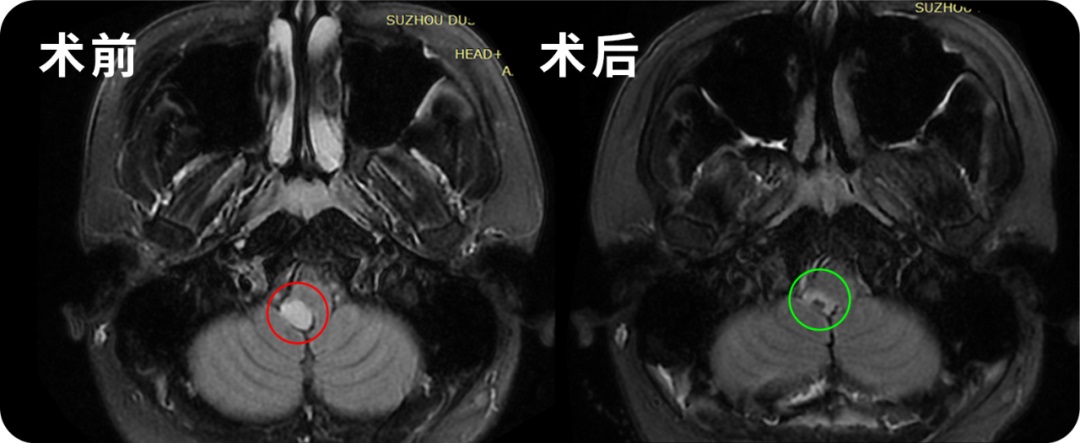

50岁女性-延髓海绵状血管瘤

术后一年,严女士在教授来华交流期间,特意来到INC拜访感谢巴教授,表示自己术后恢复很好,对于手术她满意。